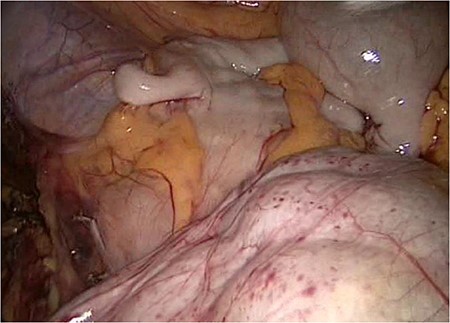

On the left side, we show the retroperitoneal pancreas, with the (as well) retroperitoneal jejunum on the right side.

The entire small bowel was found retroperitoneal covered by a slim peritoneal layer (Fig. 1). The dorsal peritoneum covering the ileum was opened (Fig. 2).

We accidentally opened the dorsal peritoneum (Fig. 2), and found the small bowel underneath - retroperitoneal (Fig. 3).